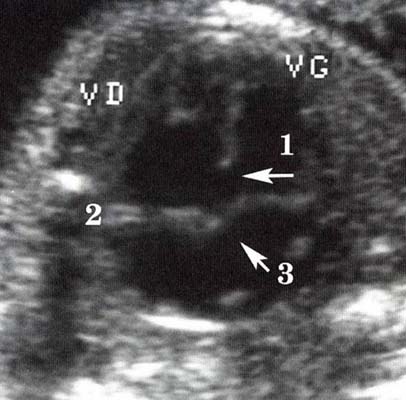

Canal atrio-ventriculaire complet